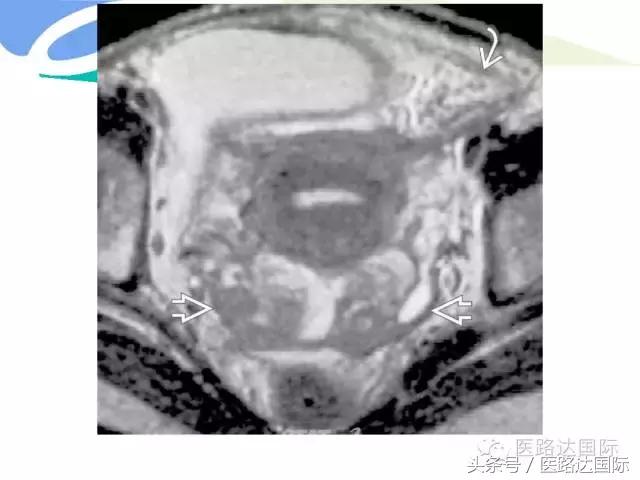

首都医科大学附属北京妇产医院梁宇霆教授从流行病学、临床特点、实验室检查、病理改变、影像学特点及治疗与预后六个方面向我们详细地介绍了女性生殖系统结核;并且着重介绍了子宫输卵管造影(HSG)的作用。在最后,梁教授还向大家介绍了如何鉴别诊断女性生殖系统结核、盆腔炎性病变和卵巢癌。

女性生殖系统结核的影像诊断及鉴别